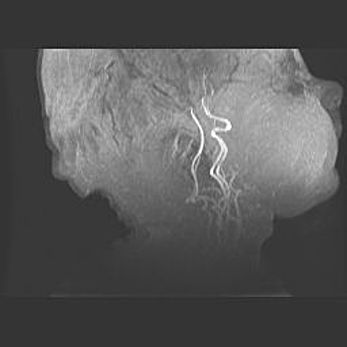

Подострая гематома правой гемисферы мозжечка.

Наружная гидроцефалия.

Возраст: 15 дней

Вес: 3100 г

Пол: женский

Окружность головы: 37 см

Срок гестации: 35-36 недель

При открытой наружной форме гидроцефалии у новорожденных расширяются и переполняются субарахноидные пространства.

Кровоизлияния в мозжечок имеют две клинико-анатомические формы: полушарные гематомы и кровоизлияния в червь.

К появлению этой патологии может привести: повреждения головного мозга, возникающие в результате асфиксии и гипоксии плода при беременности, или травмы во время родов. Редко гематома мозжечка может быть результатом первичной коагулопатии и сосудистой мальформации, диссеминированном внутрисосудистом свертывании, изоиммунной тромбоцитопении.